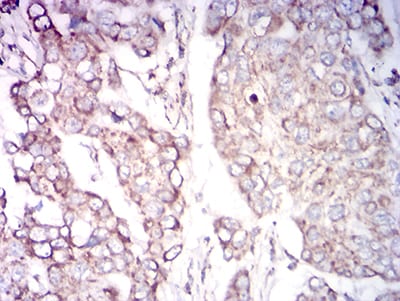

分类: 科研抗体货号: 31757别名: K18; CK-18; CYK18应用: WB,IHC,IF,FCM反应种属: Human

分类: 科研抗体货号: 31772别名: K18; CK-18; CYK18应用: WB,IHC,IF,FCM反应种属: Human